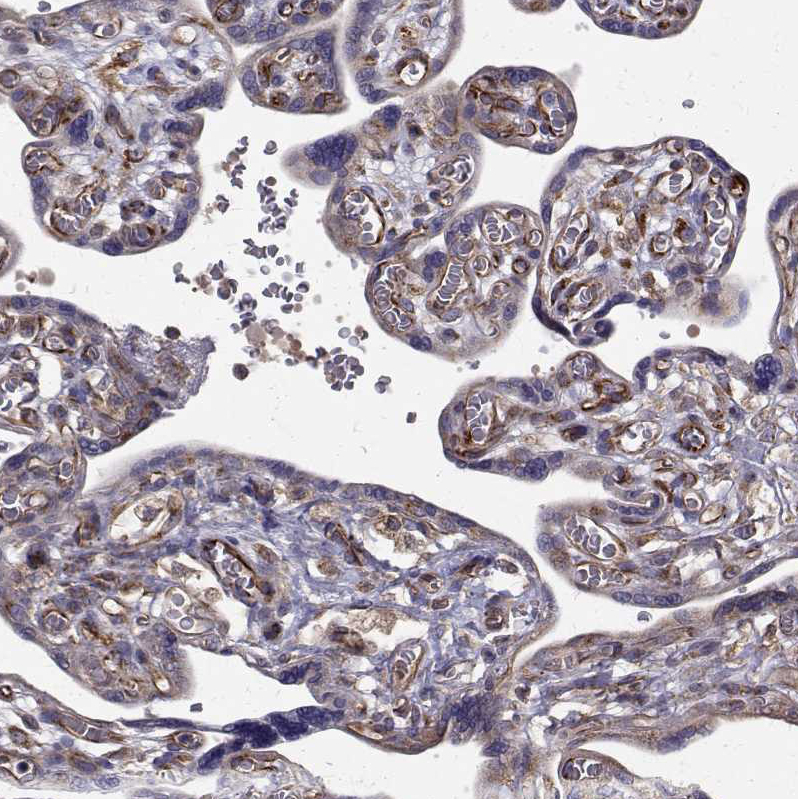

Immunohistochemical staining of human placenta shows strong cytoplasmic positivity in trophoblastic cells.